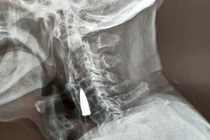

Các bác sĩ buộc phải mổ bụng người đàn ông này để có thể lấy dị vật khỏi hậu môn. Trong quá trình đó, họ đã rất sửng sốt khi nhìn thấy một quả đạn pháo dài hơn 20cm, rộng hơn 5cm.